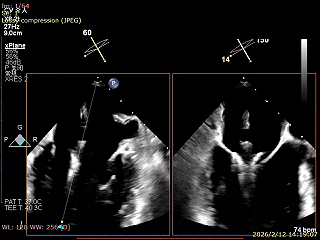

三尖瓣术前评估

三尖瓣反流(重度);肺动脉高压(中度);二尖瓣反流(中度);双房左室增大;左室顺应性减低。

术前食道超声评估

三尖瓣关闭不全重度(4+,平均缩流颈10mm),反流口以前隔、中央为主,部分后隔,瓣叶未见明显脱垂及GAP,三尖瓣环扩张(瓣环平均径43mm),二尖瓣中-重度反流,肺动脉高压(PASP:44mmHg)。